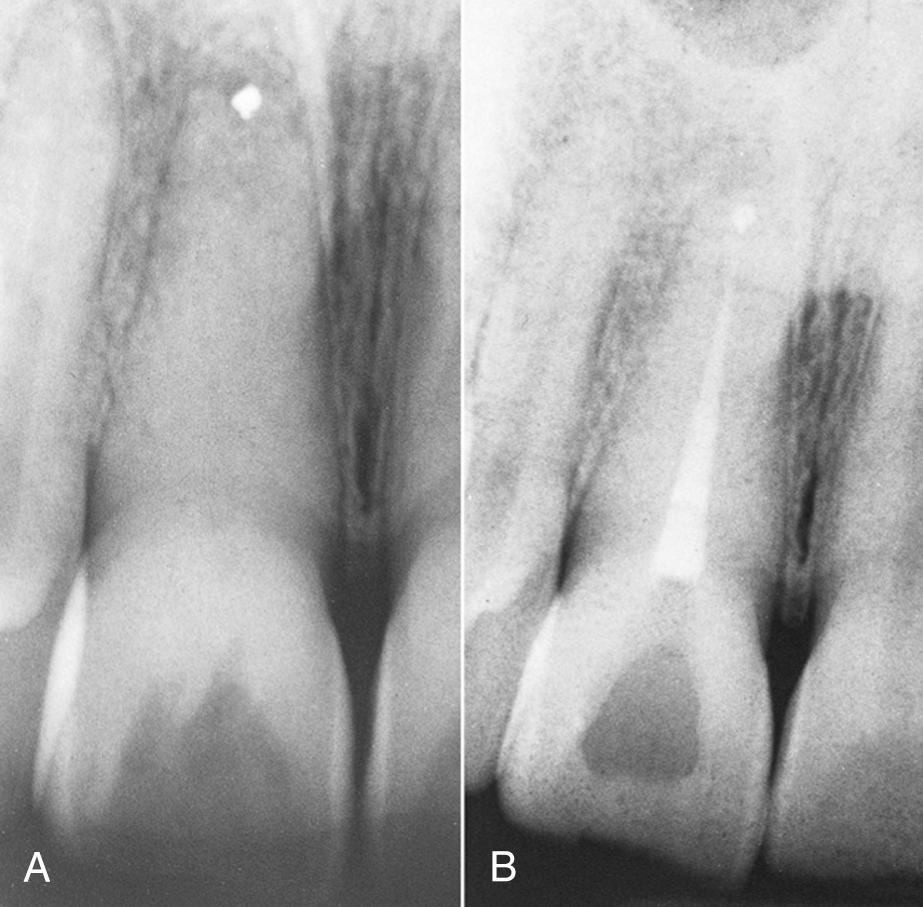

Horizontal Root Fracture

Occasionally, after a traumatic root fracture, the apical segment undergoes pulpal necrosis. Because pulpal necrosis cannot be predictably treated from a coronal approach, the apical segment is removed surgically after root canal treatment of the coronal portion ( Fig. 18.6 ).

Fig. 18.6, (A) Horizontal root fracture (arrow) , with failed attempt to treat both segments. (B) The apical segment is removed surgically, and retrograde amalgam is placed. (C) Healing is complete after 1 year.